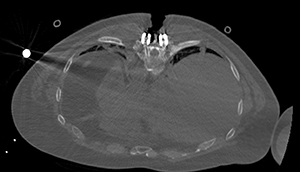

The carbon fiber material placed in Rob's back illuminate during a recent CT scan.

“This material gives us a better way to visualize the tumor,” Tran said. “If you can detect the tumor or changes in the tumor earlier, called a recurrence, you are able to treat it earlier.”